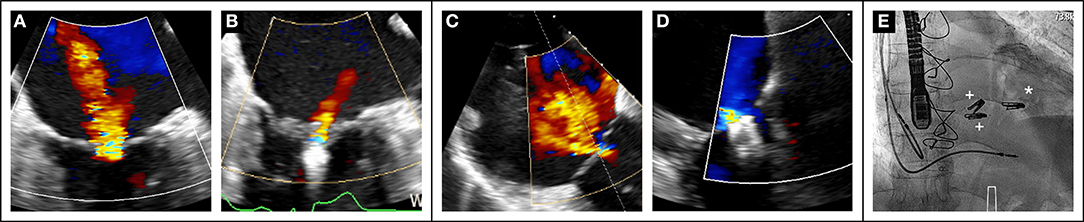

The PASCAL transcatheter mitral valve repair system (Edwards Lifesciences, Irvine, USA) has been developed to overcome some of the intrinsic technical limitations of the hitherto existing system. It has larger and longer arms, a central spacer designed to fill the coaptation defect and decrease the tension applied on the valve tissue, as well the capability to grasp each leaflet separately. After a preliminary encouraging compassionate experience in 23 patients (17), feasibility and efficacy in reducing MR have been recently confirmed in a multicenter prospective trial (18). Subsequently, the PASCAL system has gained CE mark in February 2019 for the treatment of both primary and secondary MR. Figure 1 shows an illustrative case of severe secondary MR successfully treated with implantation of one PASCAL implant.

Figure 1

Recent data (70) also suggest the importance of a global approach to combined mitral and tricuspid valve disease as illustrated in Figure 3.

Figure 3